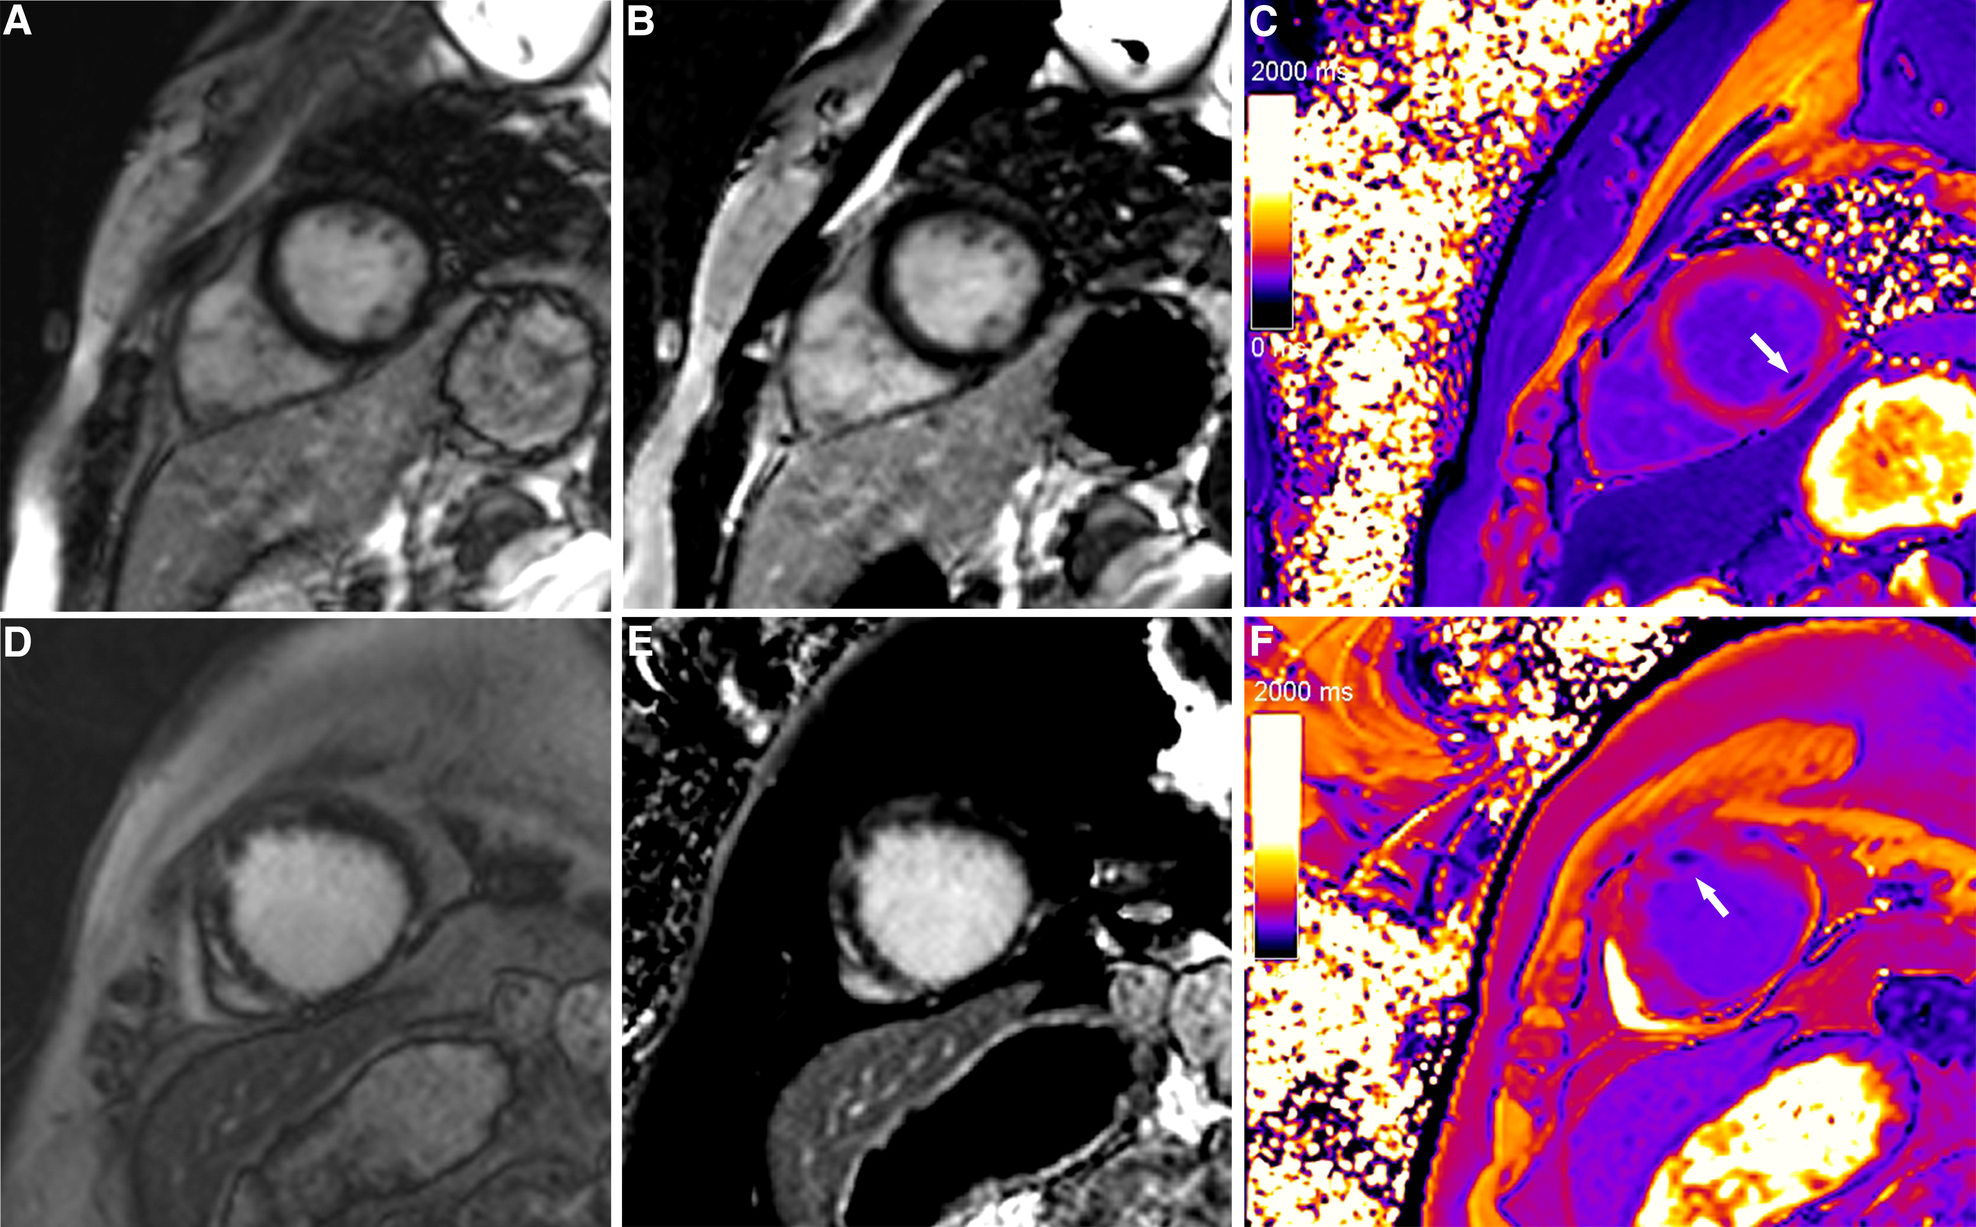

Figure 2

Typical cases in which post-contrast T1 mapping improved the detection of infarcted segments. A focal subendocardial scar was missed on magnitude (A, D) and PSIR (B, E), and an additional scar (white arrow) was identified on post-contrast T1 mapping (C, F).